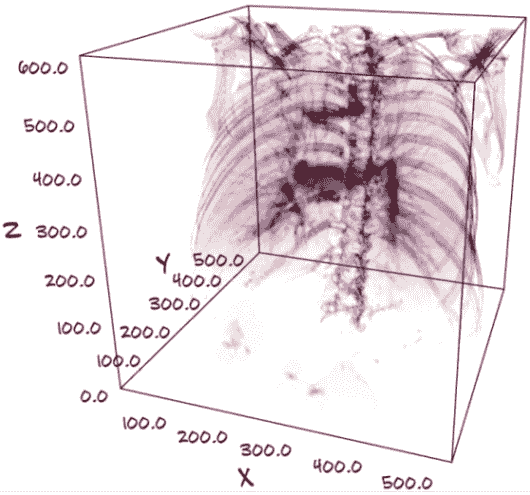

这种 3D 表示还允许我们通过隐藏我们不感兴趣的组织类型来“看到”主体内部。例如,我们可以将数据呈现为 3D,并将可见性限制在骨骼和肺组织,如图 9.2 所示。

图 9.2 显示了肋骨、脊柱和肺结构的 CT 扫描